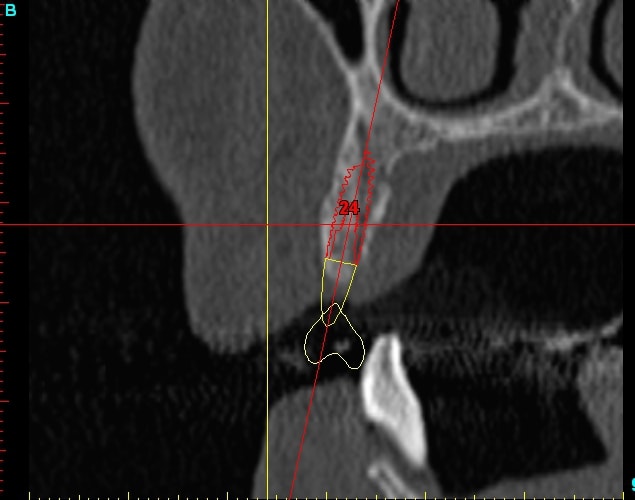

23dar fu8chl - Eugenol

Dar23 cngblb - Eugenol

24dar rfsfid - Eugenol

Dar24 scegbz - Eugenol

25dar yv2tvr - Eugenol

Dar15 gpvqe1 - Eugenol

Dar25 mrwngv - Eugenol